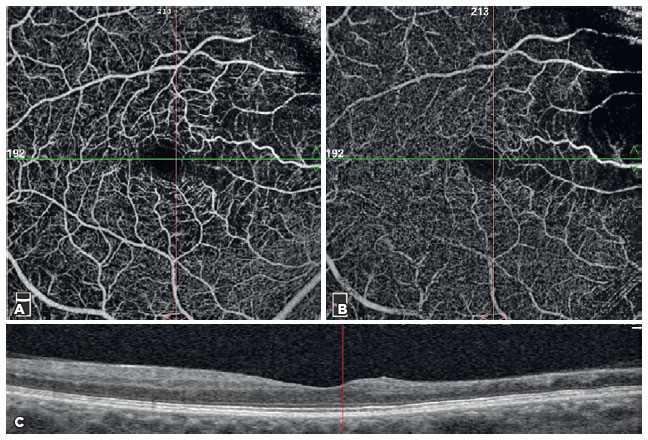

The FAZ area (mm2) in the SCP and CNP areas (mm2) was obtained via the non-flow assessment tool (Figure 3), and the FAZ area (mm2) in full retinal vasculature, FAZ perimeter (mm), acircularity index of FAZ, and foveal density (FD) (%) (foveal vessel density in a 300-µm-wide region around FAZ) were obtained via the FAZ assessment tool (Figure 4)(8). OCTA assessments were performed after resolution of RVO-ME.

06-fig03tb.jpg)

FD is a vessel density parameter within 300 microns around the FAZ in the FAZ assessment tool of OCTA. The device automatically detects the borders of the FAZ, draws another circle around the FAZ at a distance of 300 microns, and calculates the vessel density in this region(8). In our study, FD was significantly associated with the DRIL extent and CNP area (p=0.031 and p=0.022, respectively). The density assessment tool of OCTA also calculates the FD in both SCP and DCP. The device calculates the vessel density within a 1-mm diameter of the fovea-centered circle. However, these two parameters differ in that there was no significant correlation between the vessel density in the fovea in either of the macular capillary plexuses and DRIL extent and CNP area (p>0.05 for all). We hypothesized that this difference occurs because of the widened FAZ area in BRVO. As long as the FAZ widens, the FD will not be affected, because the device always measures the vessel density between the two circles (Figure 4). Nevertheless, in the vessel density assessment tool of OCTA, the circles are constant. The device automatically inserted three fovea-centered circles on the macula with diameters of 1, 3, and 6 mm (Figure 2). As the FAZ widens, the vessel density of the fovea in both SCP and DCP decreases. As a result, we suggest that, during the evaluation of the FD, the FD parameter in the FAZ assessment tool of OCTA should be used instead of the density assessment tool.

In our study, we found that the DRIL extent and CNP areas were associated with the FAZ area when using the non-flow assessment tool (p=0.031 and p=0.022, respectively). However, this association was not observed when using the FAZ assessment tool (p=0.668 and p=0.424, respectively). We hypothesized that this difference is caused by the position of segmentation lines. In the non-flow assessment tool of OCTA, both the CNP areas and FAZ area were calculated in SCP (the segmentation lines were between the ILM and inner plexiform layer). However, in the FAZ assessment tool, the FAZ area was calculated in full retinal vasculature (the segmentation lines were between the ILM and outer plexiform layer); however, the CNP area was calculated in SCP (Figures 2 and 3). Coscas et al.(10) reported that the DCP was more severely affected than the SCP in RVO.